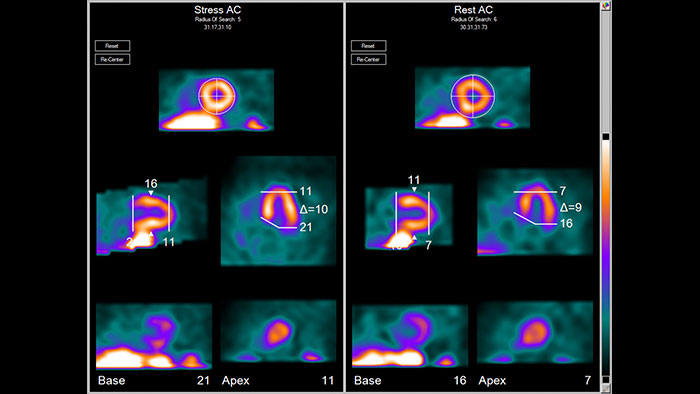

Advanced cardiac quantification

NM Cedars Sinai Cardiac Suite 2015 provides comprehensive cardiac quantification tools for gated, perfusion, and blood pool SPECT and quantitative PET. Well known by clinicians worldwide, the Cedars-Sinai Cardiac Suite 2015 application provides efficient workflow for study interpretation with exclusive integration of perfusion and function.

Benefits

SPECT and PET cardiovascular quantification, review, and reporting

NM Corridor4DM 2016* is designed for advanced cardiovascular quantification and image display and includes intelligent workflow and quality assurance measures. Quantify myocardial perfusion, function, and viability using multiple review screens, with integrated reporting through customizable templates. NM Corridor4DM 2016 also includes: LV surface estimation and quantification, additional normal databases to support, and GEMS Evolution SPECT reconstruction.